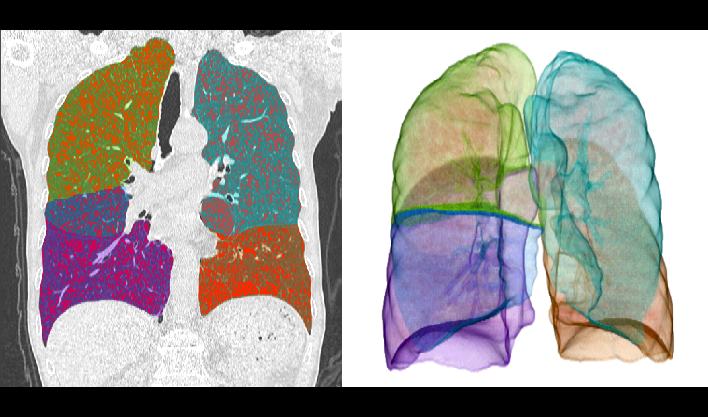

百万像素成像

1024x1024重建矩阵结合薄层成像,快速锁定微小病灶(如早期肿瘤、卒中病灶),助力急诊创伤、肿瘤筛查、卒中救治的“分秒必争"。